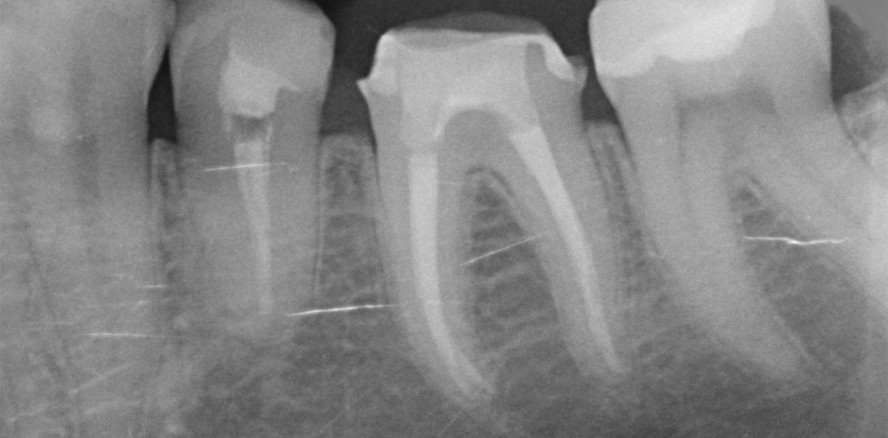

In den Fällen, in denen es zumindest radiologisch keinen offensichtlichen Grund für die persistierende bzw. neu aufgetretene Entzündung gibt, liegt die Vermutung einer bakteriellen Genese nahe.2 Eine radiologisch suffizient erscheinende Wurzelfüllung wirft die Frage auf, wie es zur Reinfektion des Wurzelkanalsystems kommen konnte (Abb. 3 und 4).

Ein möglicher Grund ist, dass der radiologische und anatomische Apex nicht immer deckungsgleich sind. Im Durchschnitt befindet sich das apikale Foramen 0,5 mm koronal dem anatomischen Apex.3 Legt man diesen Abstand für die eigene Behandlung zugrunde, macht die Einstellung des Masterpoints ca. 1 mm kürzer dem anatomischen Apex in den meisten Fällen klinisch durchaus Sinn. Bei einwurzeligen Zähnen im Frontzahn- und zum Teil auch im Prämolarenbereich kann die radiologische Längenbestimmung somit gut funktionieren. Im Molarenbereich können, aufgrund des divergierenden Verlaufs der Wurzeln zueinander, Messungen zu mehr Messfehlern führen (Abb. 5 und 6). Auch lässt sich eine orthograde Projektionsrichtung nicht immer realisieren. Pratten et al.4 verglichen in ihrer Studie 1996 die Ergebnisse einer Längenmessung mittels Radiografie in Gegenüberstellung mit dem endometrischen Verfahren und kamen zu dem Schluss, dass die Arbeitslängen bei der radiologischen Längenbestimmung tendenziell zu kurz geschätzt wurden.